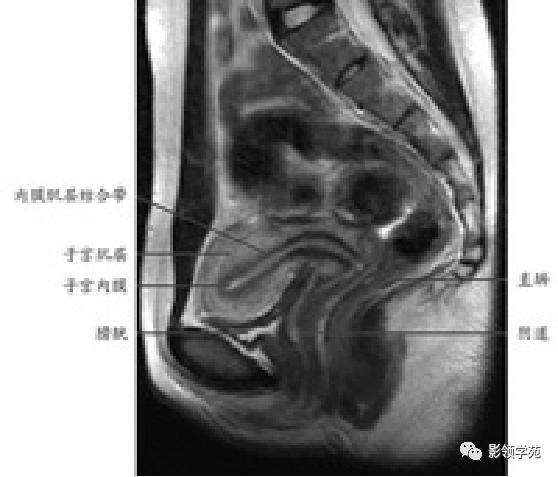

T1WI:呈均匀低信号,周围为高信号脂肪

T2WI : 宫体三层:

中心高信号---子宫内膜和分泌物;

中间低信号带---子宫肌内层,亦称结合带;

周围呈中等信号---子宫肌外层

子宫

T2WI图像可显示子宫体三层

结构

- 子宫内膜-高信号

- 结合带-低信号

- 子宫肌层-中等信号